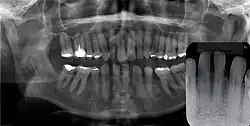

Panoramal radiograph of GCA. Inset: no evidence of bone involvement.

Gingival cyst of adult is a rare condition. The incidence is less than 0.5%. It is formed from the rests of dental lamina.[11] It is found in the soft tissues on the buccal and labial portions of the jaw. It usually occurs on the facial gingiva as a single small flesh colored swelling, sometimes with a bluish hue due to the cystic fluid. Sometimes, it may occur in cluster, either unilaterally or bilaterally or on the lingual surface of the alveolar process. It is most commonly seen in the canine and premolar regions of the mandible, and are sometimes confused with lateral periodontal cysts.[12] It is not normally problematic, but when it grows larger, it can cause some discomfort. It can be removed by simple surgical excision. They are developed late in life, generally up to the sixth decade of age.[1]